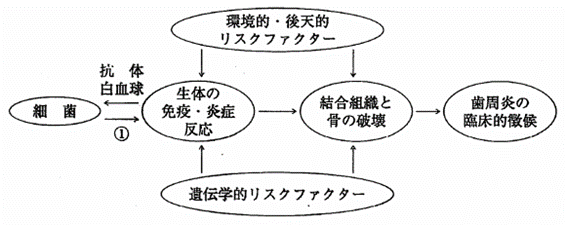

歯周炎の発症モデルを図に示す。①はどれか。1つ選べ。

a.咬合

b.毒素

c.リゾチーム

d.ラクトフェリン

解答を見る

b